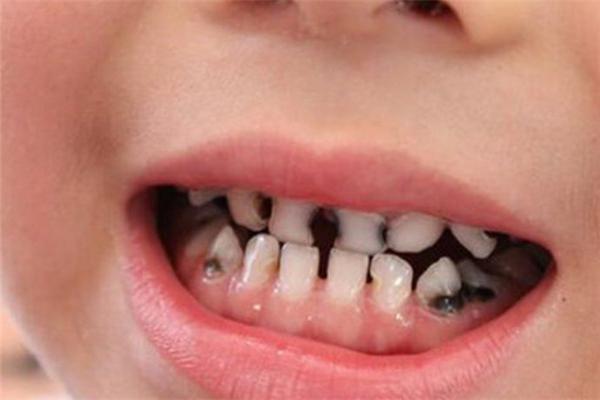

警惕!比起娃“长蛀牙”,这个高发的牙问题更容易被忽略,影响更严重

千万别觉得给孩子刷刷牙,他不长蛀牙就万事大吉,其实养个娃操心的事情真不少。在好友家儿子因为牙外伤做了根管治疗之前(对的,你没看错,根管治疗),我对牙外伤也没有特别深刻的感觉,但她跟我聊过之后,我才发现,这个问题不仅常见(小朋友难免有磕伤,磕到牙齿或者牙龈等),而且稍不留意就会忽视,之后等发现再治疗,不仅会影响了孩子恒牙的萌出,孩子要吃的苦是会翻倍的!

这件事发生以前,我没有注意到有牙外伤这回事。像很多人一样,以为没有龋齿就OK,小牙磕掉了破了一个角,或者晃动了,反正迟早要换的。

牙医说,每天都有很多来治疗牙外伤的小朋友。我们牙齿内部是中空的,里边容纳有牙髓,就像骨头里有骨髓一样。小朋友爱蹦蹦跳跳,很容易导致牙外伤,牙外伤之后容易牙髓被细菌感染发炎。